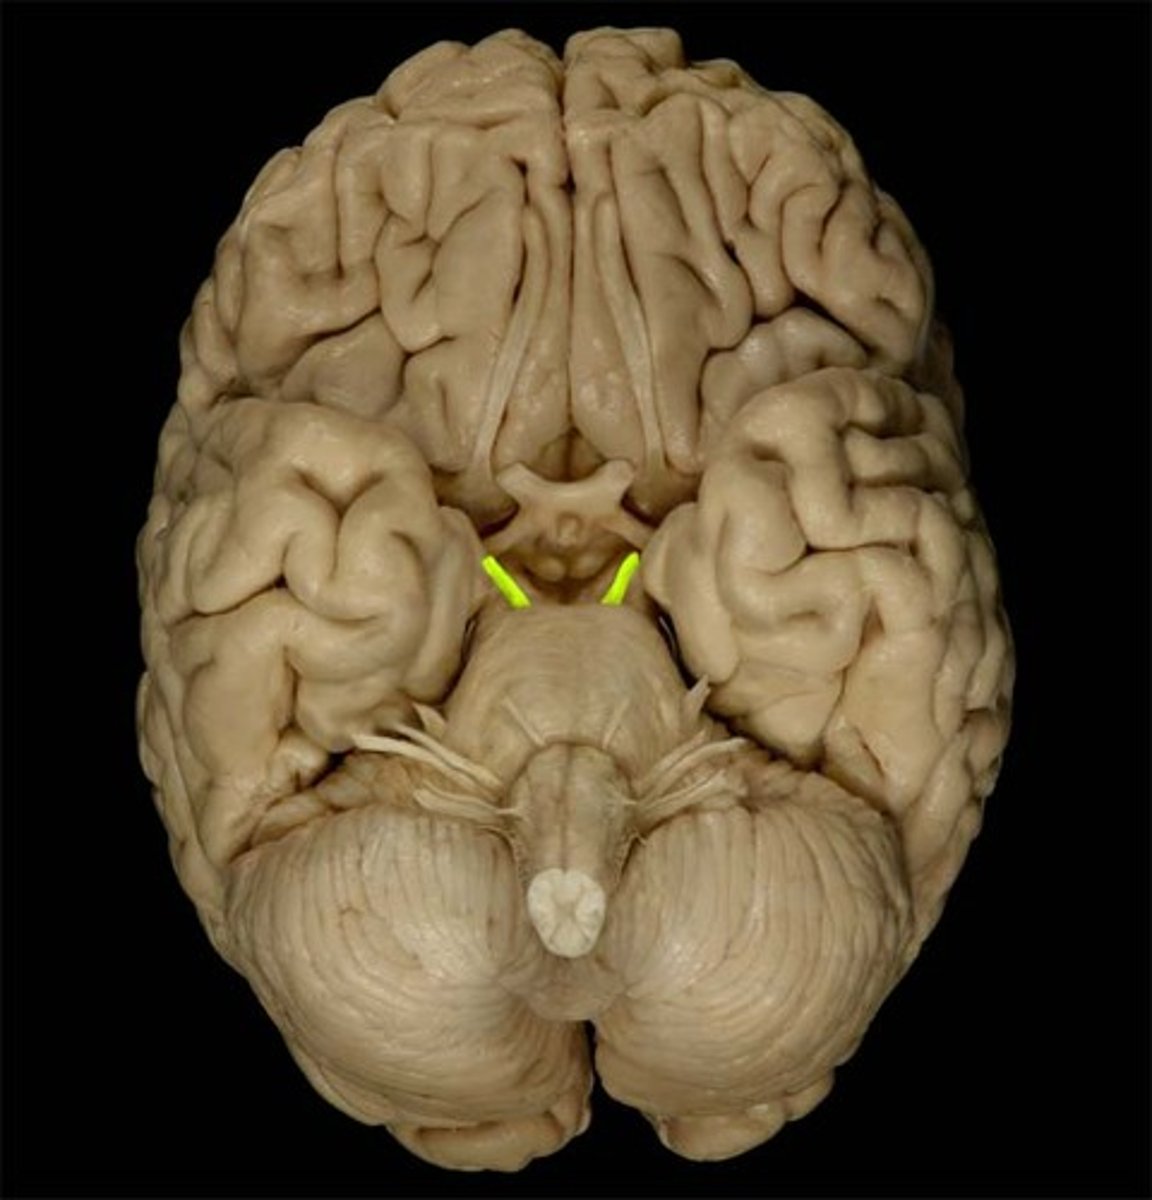

ridge of white matter extending laterally from each SUPERIOR colliculus in the corpora quadrigemini of the tectum of the midbrain

superior brachium

What is included in the lower pair of corpora quadrigemini in the tectum of the midbrain?

inferior colliculi

What is included in the upper pair of corpora quadrigemini in the tectum of the midbrain?

superior colliculi

ridge of white matter extending laterally from each INFERIOR colliculus in the corpora quadrigemini of the tectum of the midbrain

inferior brachium

small region located just ventral and rostral to the superior colliculus that is important for the pupillary light reflex

pretectal area

Which cranial nerve emerges just caudal to the inferior colliculus?

CN IV